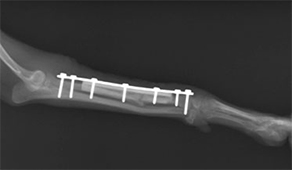

前肢橈尺骨骨折

1kg〜4kgの超小型犬が、室内でソファや抱っこの状態から飛び降りるくらいのことで骨折する場合が多いです。特に人気犬種のTプードルやチワワなどに多く認められます。

手術前

手術後

1.6kgのトイプードルの橈尺骨骨折です。プレートおよびスクリューを用いて固定、治療しました。